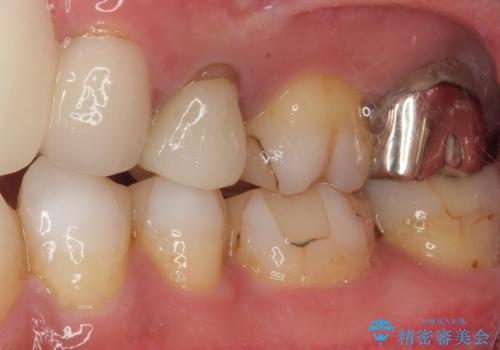

- 数日前から左下の奥歯がズキズキと脈をうつような痛みがあるとのことで来院された患者様です。

精査の結果、左下の第一小臼歯の虫歯が大きく進行していることが原因で痛みが出ていることがわかりました。

ラバーダム防湿を行ったうえで根管治療を行い、その後オールセラミッククラウンによる補綴治療を行っていくこととしました。